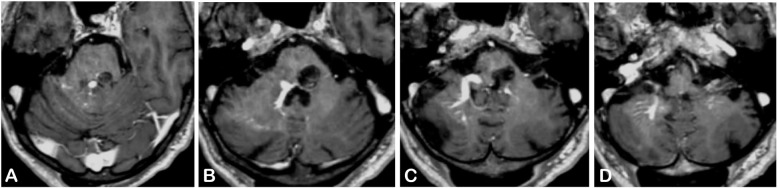

圖2:腦部核磁共振成像顯示(a白色箭頭,增強(qiáng)后T1加權(quán)序列)腦干海綿狀血管畸形(BCM)與(A,B,C黑色箭頭,增強(qiáng)后T1加權(quán)序列)雙側(cè)小腦發(fā)育性靜脈異常(DVA),位于右側(cè),流入Galen靜脈。(B黑色箭頭,增強(qiáng)后T1加權(quán)序列和D,后箭頭,梯度回波序列)BCM負(fù)責(zé)腦橋內(nèi)側(cè)血腫